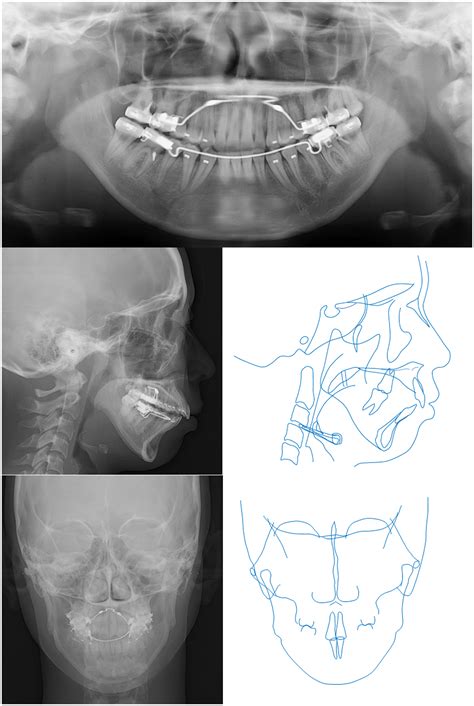

To confirm a diagnosis of Idiopathic Condylar Resorption, specialists use a multi-faceted approach. A physical exam is rarely sufficient; advanced imaging is essential. A Cone Beam Computed Tomography (CBCT) scan is the gold standard for visualizing the condylar heads and determining the extent of bone loss. MRI scans may also be utilized to evaluate the condition of the articular disc within the joint. By comparing serial radiographs over several months, an oral and maxillofacial surgeon can track the rate of resorption to determine if the condition is currently active or stable.

• Orthognathic Surgery: Once the condition has been deemed "stable" (the resorption has stopped), jaw surgery may be performed to correct the bite and facial structure.

One of the most critical aspects of treatment is timing. If a surgeon performs corrective surgery while the resorption is still active, there is a high risk that the new jaw position will not be maintained, and the bone will continue to resorb post-operatively. Therefore, proving clinical stability through serial imaging is a mandatory precursor to any surgical intervention.